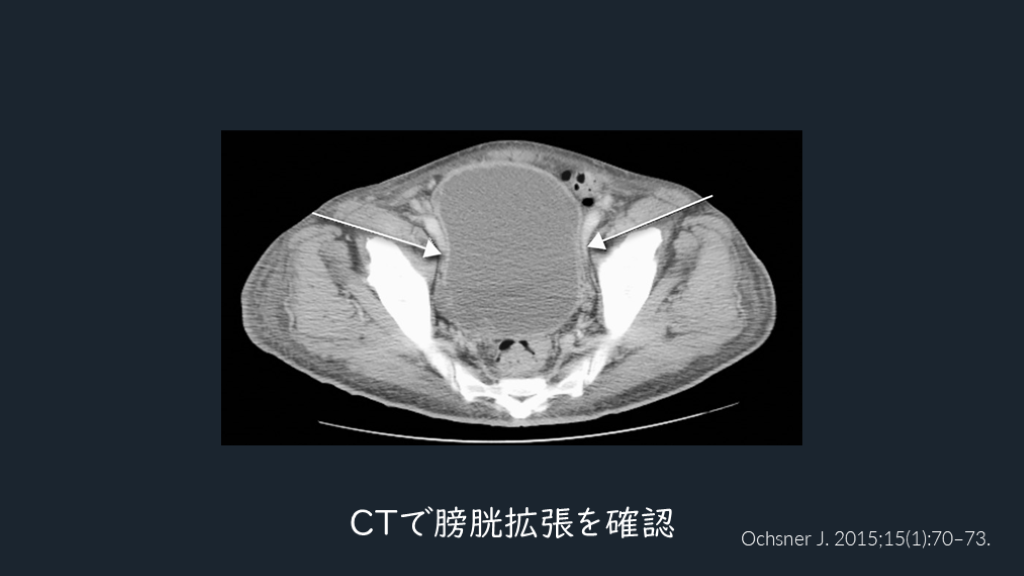

脊髄障害は わかりにくかったりする。 運動感覚障害・膀胱直腸障害を ヒントに。CTでの膀胱所見も。 TIPS

CTで膀胱見てみる。 しっかりした脊髄障害では膀胱直腸障害はないか?を意識して所見を確認する。 CTでの膀胱が緊満しているさまもみる。 脊髄梗塞の鑑別には、CTで大動脈解離も気にする。 解説 Neurologia . 2023;38(6):391-398.

Ochsner J. 2015;15(1):70–73. CTで膀胱拡張を確認